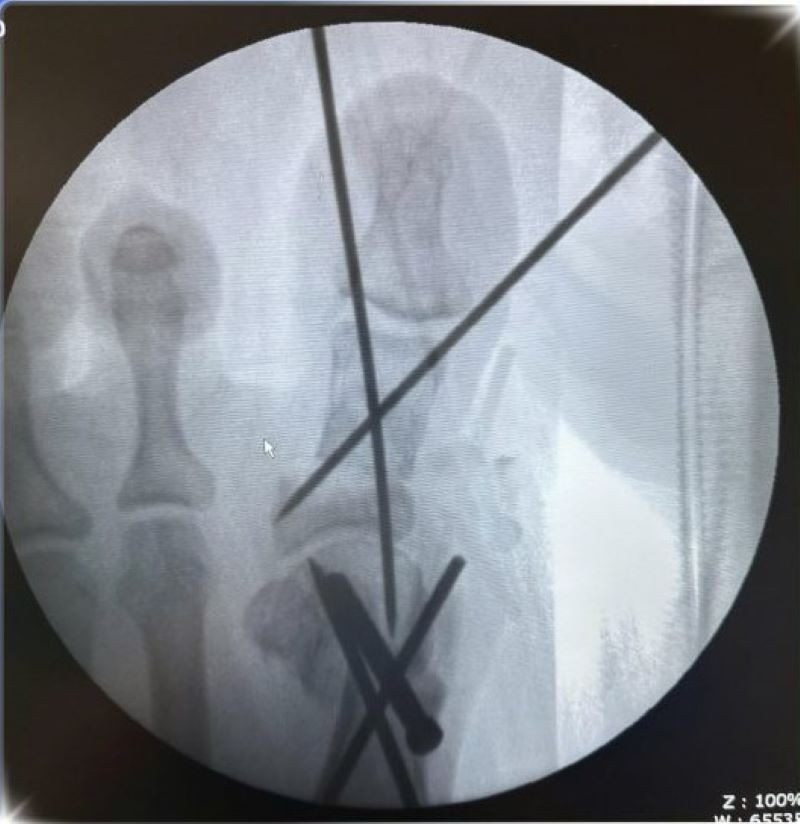

Ca phẫu thuật được tiến hành dưới sự hỗ trợ của hệ thống C-arm, thiết bị chẩn đoán hình ảnh trong mổ, giúp bác sĩ xác định chính xác vị trí cần can thiệp. Quá trình bao gồm: cắt xương, nắn chỉnh trục ngón cái, cố định bằng đinh và vít, sau đó khâu đóng và băng ép vết mổ.

Hình ảnh cận lâm sàng - Ảnh BVCC